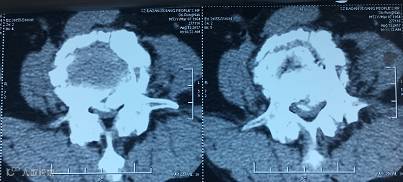

【术前CT】